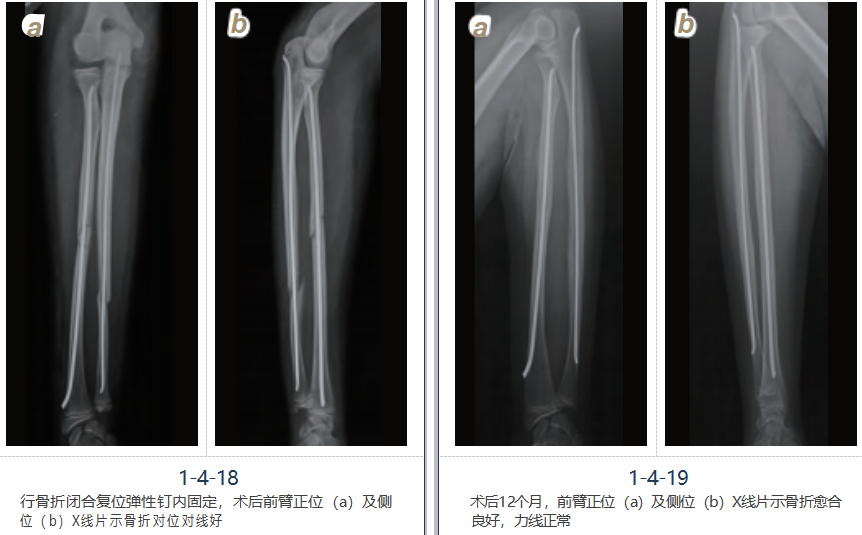

病例三

男,12岁,摔伤致右前臂肿胀、压痛、畸形、活动受限,诊断为右尺桡骨骨折,行右尺 桡骨骨折闭合复位弹性钉内固定术,术后恢复良好(图1-4-17~19)。